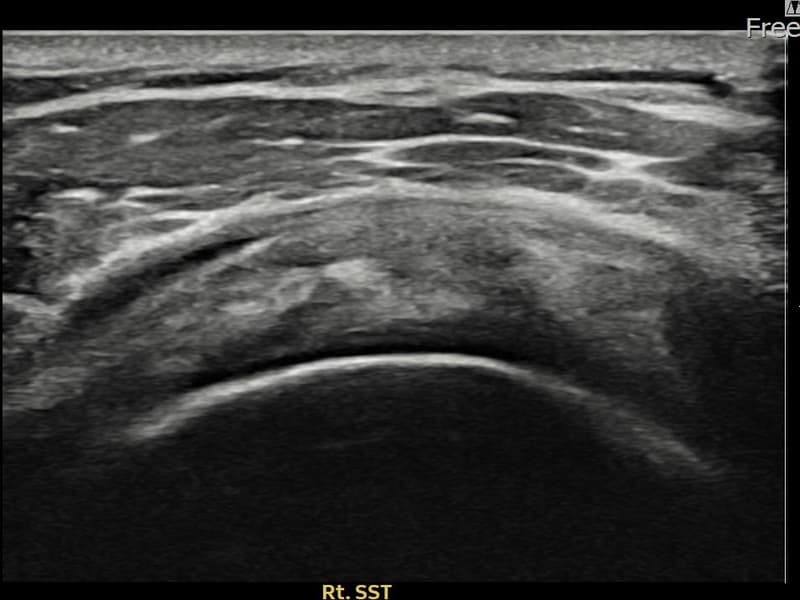

术后

术前超声确认右侧 견갑하근건 关节面侧部分撕裂,右侧冈上肌腱回声不连续伴肌腱缺损(7mm × 3mm (肌腱厚度约28%缺损))。术后超声显示撕裂部位充满再生组织,肌腱连续性恢复,回声模式正常化。

该患者持续肩痛。详细超声检查确认右侧 견갑하근건 关节面侧部分撕裂(缺损:7mm × 3mm (肌腱厚度约28%缺损))。在超声引导下实施非手术缩小缝合术。术后佩戴支具约4-6周,随后进行分阶段康复锻炼。随访超声确认肌腱连续性恢复、结构稳定,患者顺利回归日常生活。